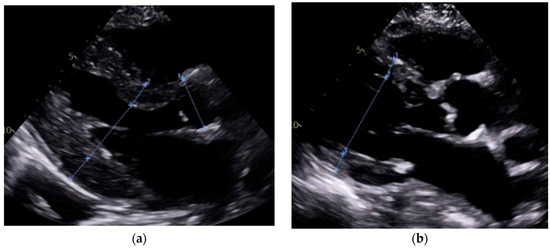

Our study found significantly greater IVSd and LVPWd in amyloidosis compared to sarcoidosis, consistent with prior reports on echocardiographic findings in amyloidosis namely, pronounced LV wall thickening and diastolic dysfunction (Figure 1 and Figure 2). Ref [24], Conversely, TTE offers limited sensitivity in sarcoidosis, functioning mainly to prompt further diagnostic imaging when regional wall thinning or basal septal changes are detected [25]. Our CMR findings revealed focal or patchy LGE in sarcoidosis, as well as mismatch uptake patterns on PET, which parallels the existing literature that utilizes CMR for structural analysis and FDG PET for monitoring active inflammation [26,27]. Our findings in the CA cohort corroborate that PYP scintigraphy (with a negative monoclonal protein screen) remains highly specific for transthyretin cardiac amyloidosis [28]. Additionally, all 19 of our CA patients undergoing CMR exhibited a diffuse pattern of LGE, highlighting the global amyloid infiltration of myocardium in contrast to the patchy granulomatous infiltration in CS. More specific measures on CMR such as Native T1 mapping and ECV measurements can indicate the extent of amyloid infiltration [29]. Unfortunately, only 19 of the 125 amyloidosis patients underwent CMR in our study, which limited the robustness of sub-analyses in this domain (Figure 3 and Figure 4).

Figure 2.

Apical four-chamber transthoracic echocardiography (TTE) comparison. (a) Cardiac amyloidosis is characterized by thickened ventricular walls, small ventricular chambers, and biatrial enlargement, consistent with restrictive cardiomyopathy. (b) Cardiac sarcoidosis showing relatively normal wall thickness, patchy wall thinning (often basal septum), and regional motion abnormalities, with atrial enlargement.